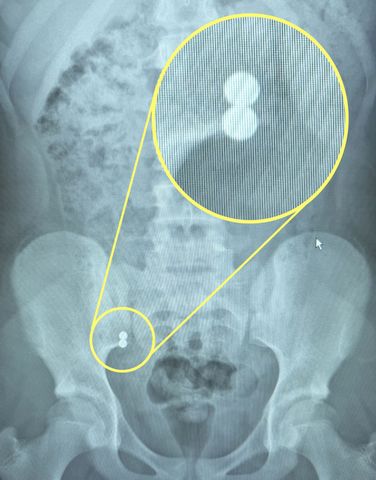

Bignell rushed her daughter to the emergency room, where an X-ray confirmed that Bella had, indeed, swallowed two of the magnets.

"They attract, because they're magnets, and they ripped through her appendix, separated again and ripped through her bowel. She had her appendix and part of her bowel cut out. It's very serious. When the doctors were telling me I was in tears, because you don't know the damage it's caused inside."